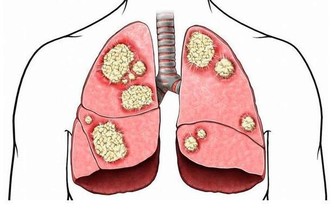

檢查方法及高危人群

通過頸動脈彩超,頭顱CT、MR或腦血管造影等檢查可明確哪些血管閉塞、哪條血管狹窄,從而進行有針對性的治療。另外,高血壓、高血脂、高同型半胱氨酸血症、糖尿病、冠心病、年齡大於55歲、肥胖以及吸煙酗酒者都是中風的高危人群,更應該控制危險因素。